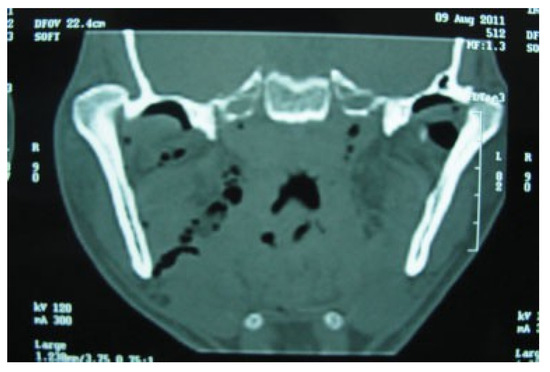

Superolateral Dislocation of Bilateral Intact Condyles—An Unusual Presentation: Report of a Case and Review of Literature

:1. Case Report